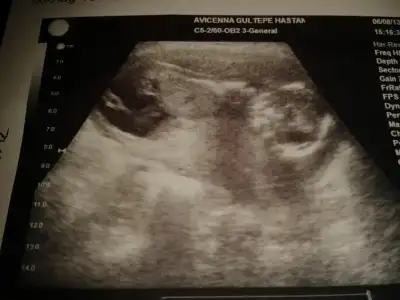

$2013-08-11 22.42.25.webp

kızlar benim resimlerede bi yorum yapın ne acaba?ben anlayamadım.çabuk yazın çok merak ediyorum:49: